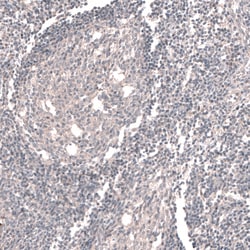

Invitrogen™ ACSL3 Polyclonal Antibody

Brand: Invitrogen™ PA582427

| Immunohistochemistry (Paraffin), Western Blot | |